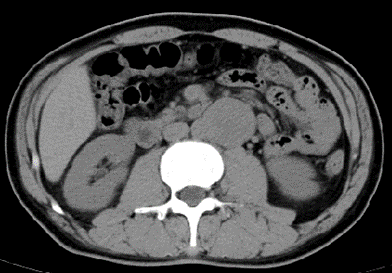

l CT:腹膜后腹主动脉旁软组织密度肿块,边界清,约4.2*4.3cm,密度不均,增强扫描皮髓质不均匀强化,实质期强化稍低,排泌期进一步减低。左肾2.0*2.3cm囊状低密度影。结论:左侧腹膜后占位,副神经节瘤?,左肾囊肿